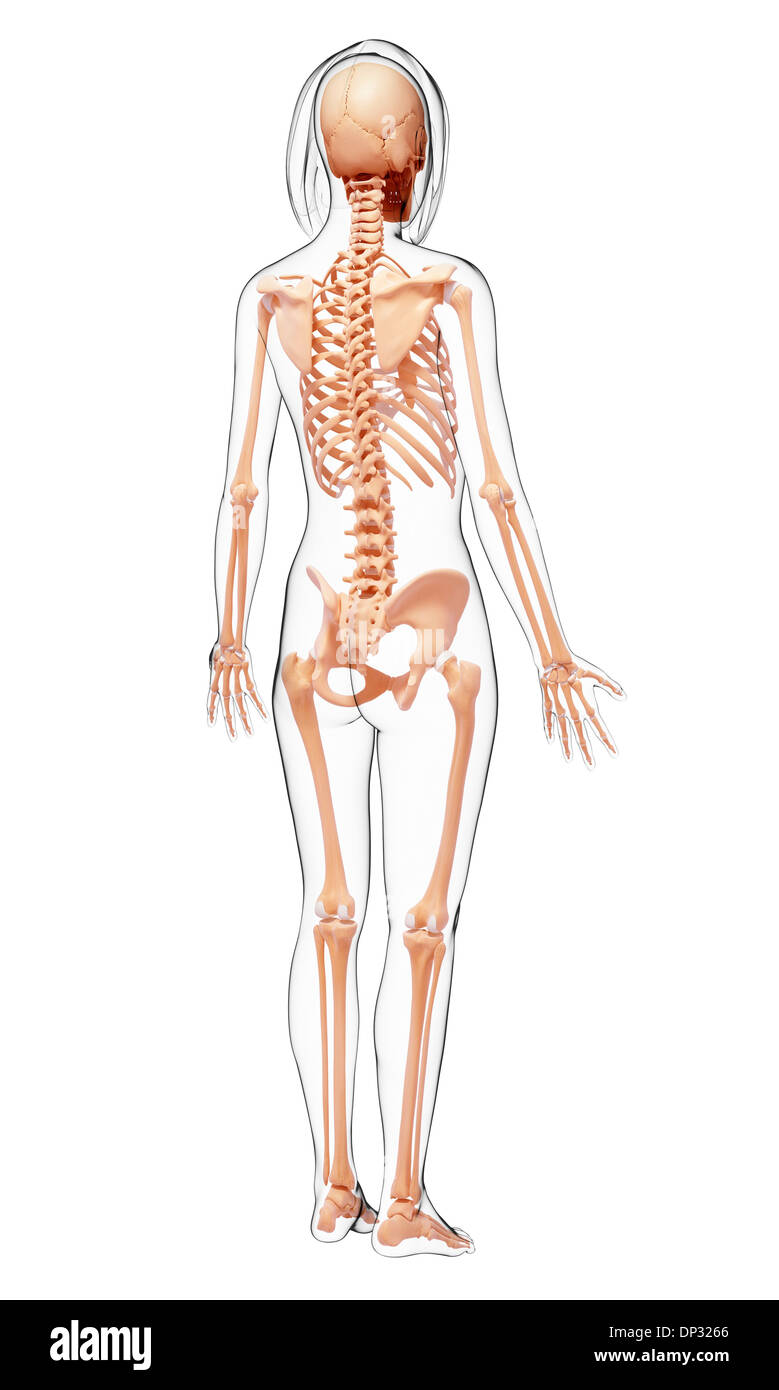

Human Skeleton, artwork Banque D'Imageshttps://www.alamyimages.fr/image-license-details/?v=1https://www.alamyimages.fr/human-skeleton-artwork-image65260917.html

Human Skeleton, artwork Banque D'Imageshttps://www.alamyimages.fr/image-license-details/?v=1https://www.alamyimages.fr/human-skeleton-artwork-image65260917.htmlRFDP4TY1–Human Skeleton, artwork